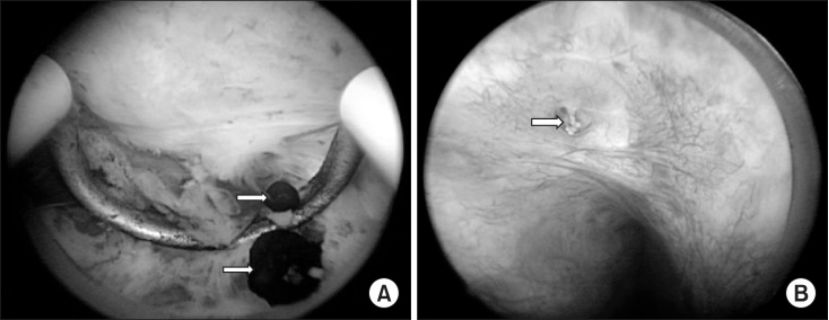

图为内窥镜下的前列腺结石,A为内源性结石,B为外源性结石

原来,前列腺结石分为“内源性结石”和“外源性结石”,内源性结石一般指存在于前列腺腺体之内的结石,多由慢性炎症导致的前列腺腺管阻塞,前列腺液浓缩,各种成分混合并钙化所致,此类结石可含较多细菌;而外源性结石则指的是尿液反流形成的位于前列腺部尿道中的结石,类似于肾、输尿管结石,结石较大时可能导致尿路刺激症状、尿道狭窄并引起排尿困难。我们一般说的前列腺结石多指“内源性结石”。